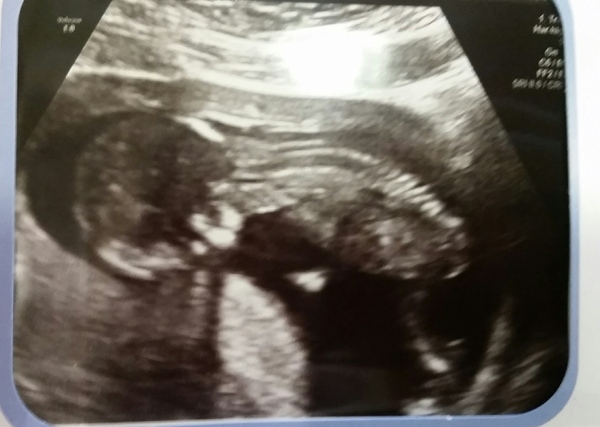

Treaclepie19 · 18/03/2015 11:36

All is fine with little one!

Dated ahead (which is odd!) So due date is now 19th September :) (not DH'S birthday anymore) 13+4 today

Nuchal was 2.1, had all my blood tests and everything. Consultant says I can be midwife led.

Little one was very fidgety and upside down, they kept sitting up straight and headbutting me :p 20 week scan is on the 11th May.

Eek :D

Aw little upside down baby, great pic :)